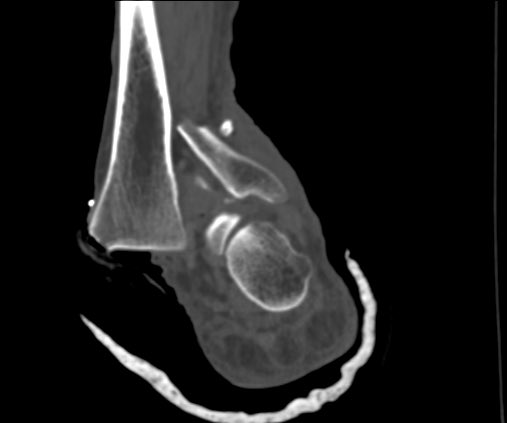

Clinical correlation needed

#exposedfracture#ortho#mskrad#radiologypic.twitter.com/BopZtsmPfI